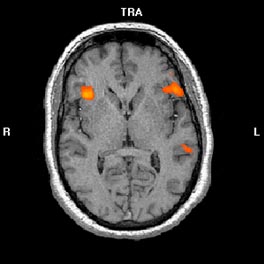

En nuestra experiencia clínica con pacientes con ELT izquierda encontramos resultados que concuerdan con la literatura previa, ya que existe una organización atípica del lenguaje en este tipo de pacientes donde se obtienen activaciones de menor dominancia izquierda (ver Figuras 1A Y 1B).

Activación cerebral bilateral durante la tarea de fluidez fonética (1A) y generación verbal (1B) en un paciente con ELT izquierda con una dominancia manual preferentemente diestra evaluada mediante el Edinburgh Handedness Inventory

| 1A.- Fluidez fonética |

1B.- Generación verbal |